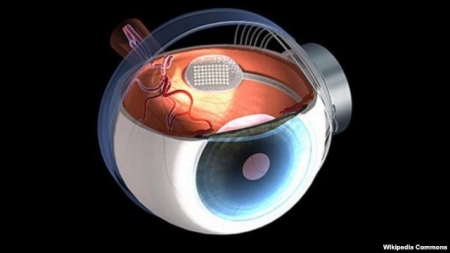

وہ دن اب کچھ زیادہ دور نہیں ہے جب بینائی سے محروم افراد اپنے اردگرپھیلے ہوئے رنگوں کو دیکھ سکیں گے کیونکہ سائنس دانوں نے حال ہی میں مصنوعی آنکھ بنانے میں نمایاں کامیابی حاصل کی ہے۔

بینائی پر تحقیق کرنے والے سائنس دانوں نے دعویٰ کیا ہے کہ وہ آنکھ کے پردے میں موجود اس خلیے کے کوڈ تک پہنچنے میں کامیاب ہوگئے ہیں جو دماغ کو برقی پیغام بھیجتا ہے۔ دیکھنا ایک پیچیدہ عمل ہے اور کسی چیز کی طرف دیکھنے اور اس کے نظر آنے کے درمیان کئی مرحلے ہیں۔ ہوتا یوں ہے کہ جب ہم کسی چیز کو دیکھتے ہیں تو آنکھ کا عدسہ بصارتی پردے پر اس کی الٹی تصویر بناتا ہے۔ یہ پردہ ڈیجیٹل کیمرے کے سینسر کی طرح کام کرتا ہے او برقی لہروں کے ذریعے تصویر کو فوراً دماغ کے اس حصے میں منتقل کردیتا ہے جس کا تعلق دیکھنے سے ہے۔ دماغ اس کا موازنہ یادشتوں سے کرتا ہے اور ہمیں پتا چل جاتا ہے ہم کیا دیکھ رہے ہیں یااس چیز کا رنگ کیا ہے۔ دیکھنے کا عمل دماغ میں انجام پاتا ہے، آنکھ محض ایک ابتدائی کام کرتی ہے۔اگر دماغ کا بصارتی حصہ درست کام کررہاہو تووہ مصنوعی آنکھ سے پیغامات وصول کرکے چیزوں کو دیکھ سکتا ہے۔ لیکن اگر اس حصے میں کوئی خرابی ہوتو دیکھنے کا عمل درست طورپر انجام نہیں پاسکتا۔ آنکھ کے پردے پر روشنی پڑنے سے اس کے خلیوں میں ایک مخصوص برقی نقش بنتے ہیں ۔بصارتی خلیوں کے کوڈ تک رسائی کے بعد سائنس دانوں نے مصنوعی بصارتی پردہ تیار کیا جسے انہوں نے ایک ایسے چوہے کی آنکھ میں لگایا جو مکمل طور پر اندھا تھا۔ آلہ نصب ہونے کے بعد چوہے تقریباً نارمل انداز میں دیکھنے کے قابل ہوگیا۔ مصنوعی آنکھ کی تیاری پر ایک عرصے سے کام ہورہاہے ، لیکن اس سے پہلے تک کوئی قابل ذکر کامیابی حاصل نہیں ہوئی۔اب تک بننے والی بہترین مصنوعی آنکھ جن مریضوں کو لگائی گئی وہ صرف روشن اور کالے دھبے دیکھنے کے قابل ہوسکے تھے۔جب کہ نئی مصنوعی آنکھ دماغ کو وہی سنگنلز ملتے ہیں جو حقیقی آنکھ کےبصارتی خلیے بھیجتے ہیں۔ نیشنل اکیڈمی آف سائنسز کے جریدے میں شائع ہونےتحقیق میں کہا گیا ہے کہ ماہرین کو یقین ہے کہ نئی مصنوعی آنکھ بہت سے لوگوں کی زندگیاں یکسر تبدیل کردے گی۔ نیویارک کی کارنل یونیورسٹی کی ڈاکٹر شیلا نیرن برگ نے ، جو اس تحقیق کی قیادت کررہی ہیں، کہاہے کہ بصارتی خلیے کا استعمال کرنے سے آنکھ کی کارکردگی اسی طرح بہتر ہوئی ہے جیسے کوئی تصویر ریزولوشن بڑھانے سے زیادہ واضح ہوجاتی ہے۔ دنیا بھر کے طبی سائنس دان طویل عرصے سے بینائی کے اس مرض کا علاج ڈھونڈنے کی کوشش کررہے ہیں جس میں مبتلا ہوکر مریض آہستہ آہستہ بینائی سے مکمل طورپر محروم ہوجاتا ہے۔ یہ مرض بصارتی پردے کے روشنی محسوس کرنے والے خلیو ں کو تباہ کردیتا ہے ، جب کہ آنکھ اور دماغ کااعصابی تعلق قائم رہتا ہے۔ اس مرض کے باعث دنیا بھر تقریباً دو کروڑ افراد ایسے ہیں جو یا تو اپنی بصارت کھوچکے ہیں یا پھر رفتہ رفتہ ان کی زندگی میں تاریکی بڑھ رہی ہے۔ سائنس دانوں کو توقع ہے کہ ان مریضوں کی آنکھوں میں مصنوعی پردہ لگانے سے ان کی بینائی واپس آجائے گی۔ ماہرین کا کہناہے کہ دیکھنے کے لیے صرف ریزولوشن بڑھانا ہی کافی نہیں ہے۔ اصل کام روشنی کی لہروں کو ایسے پیغامات میں تبدیل کرنا ہےجسے دماغ پڑھ سکتا ہو۔ نئی مصنوعی آنکھ میں اسی پہلو کو مدنظر رکھا گیا ہے۔ سائنس دانوں کا کہناہے کہ اندھے چوہے کی آنکھ میں مصنوعی بصارتی پردہ لگانے سے اس کی90 فی صد بینائی واپس آجانے کے بعد لاکھوں انسانوں کی زندگیوں میں روشنی لانے کا راستہ کھل گیا ہے۔